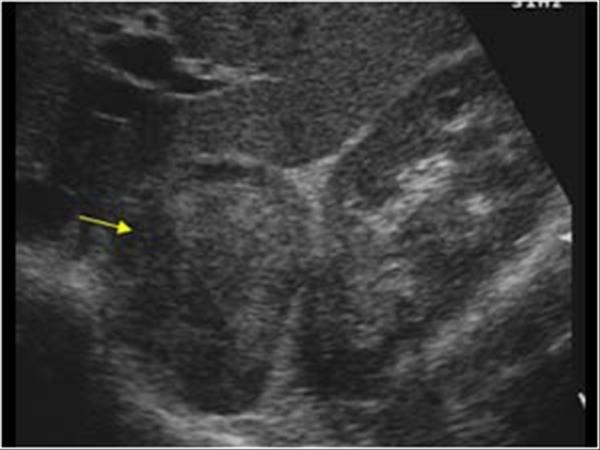

Most common solid renal mass in adults

hematuria

flank pain

palpable mass

lung mets

Renal Cell Carcinoma

Most common solid renal mass in adults

hematuria

flank pain

palpable mass

lung mets

Renal Cell Carcinoma

generally appear as hypoechoic or diffuse enlargement